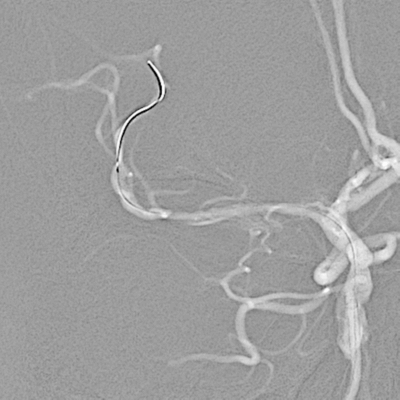

脑血管造影:右侧大脑中动脉M1段闭塞,代偿不足。

左椎动脉V4段重度狭窄。

选取工作角度造影,测量病变长度。

微导丝辅助微导管通过闭塞段,以赛诺神畅Neuro LPS-1.5-15mm球囊分次扩张闭塞段。

球扩后造影见闭塞段恢复正向血流M1段远端夹层表现。